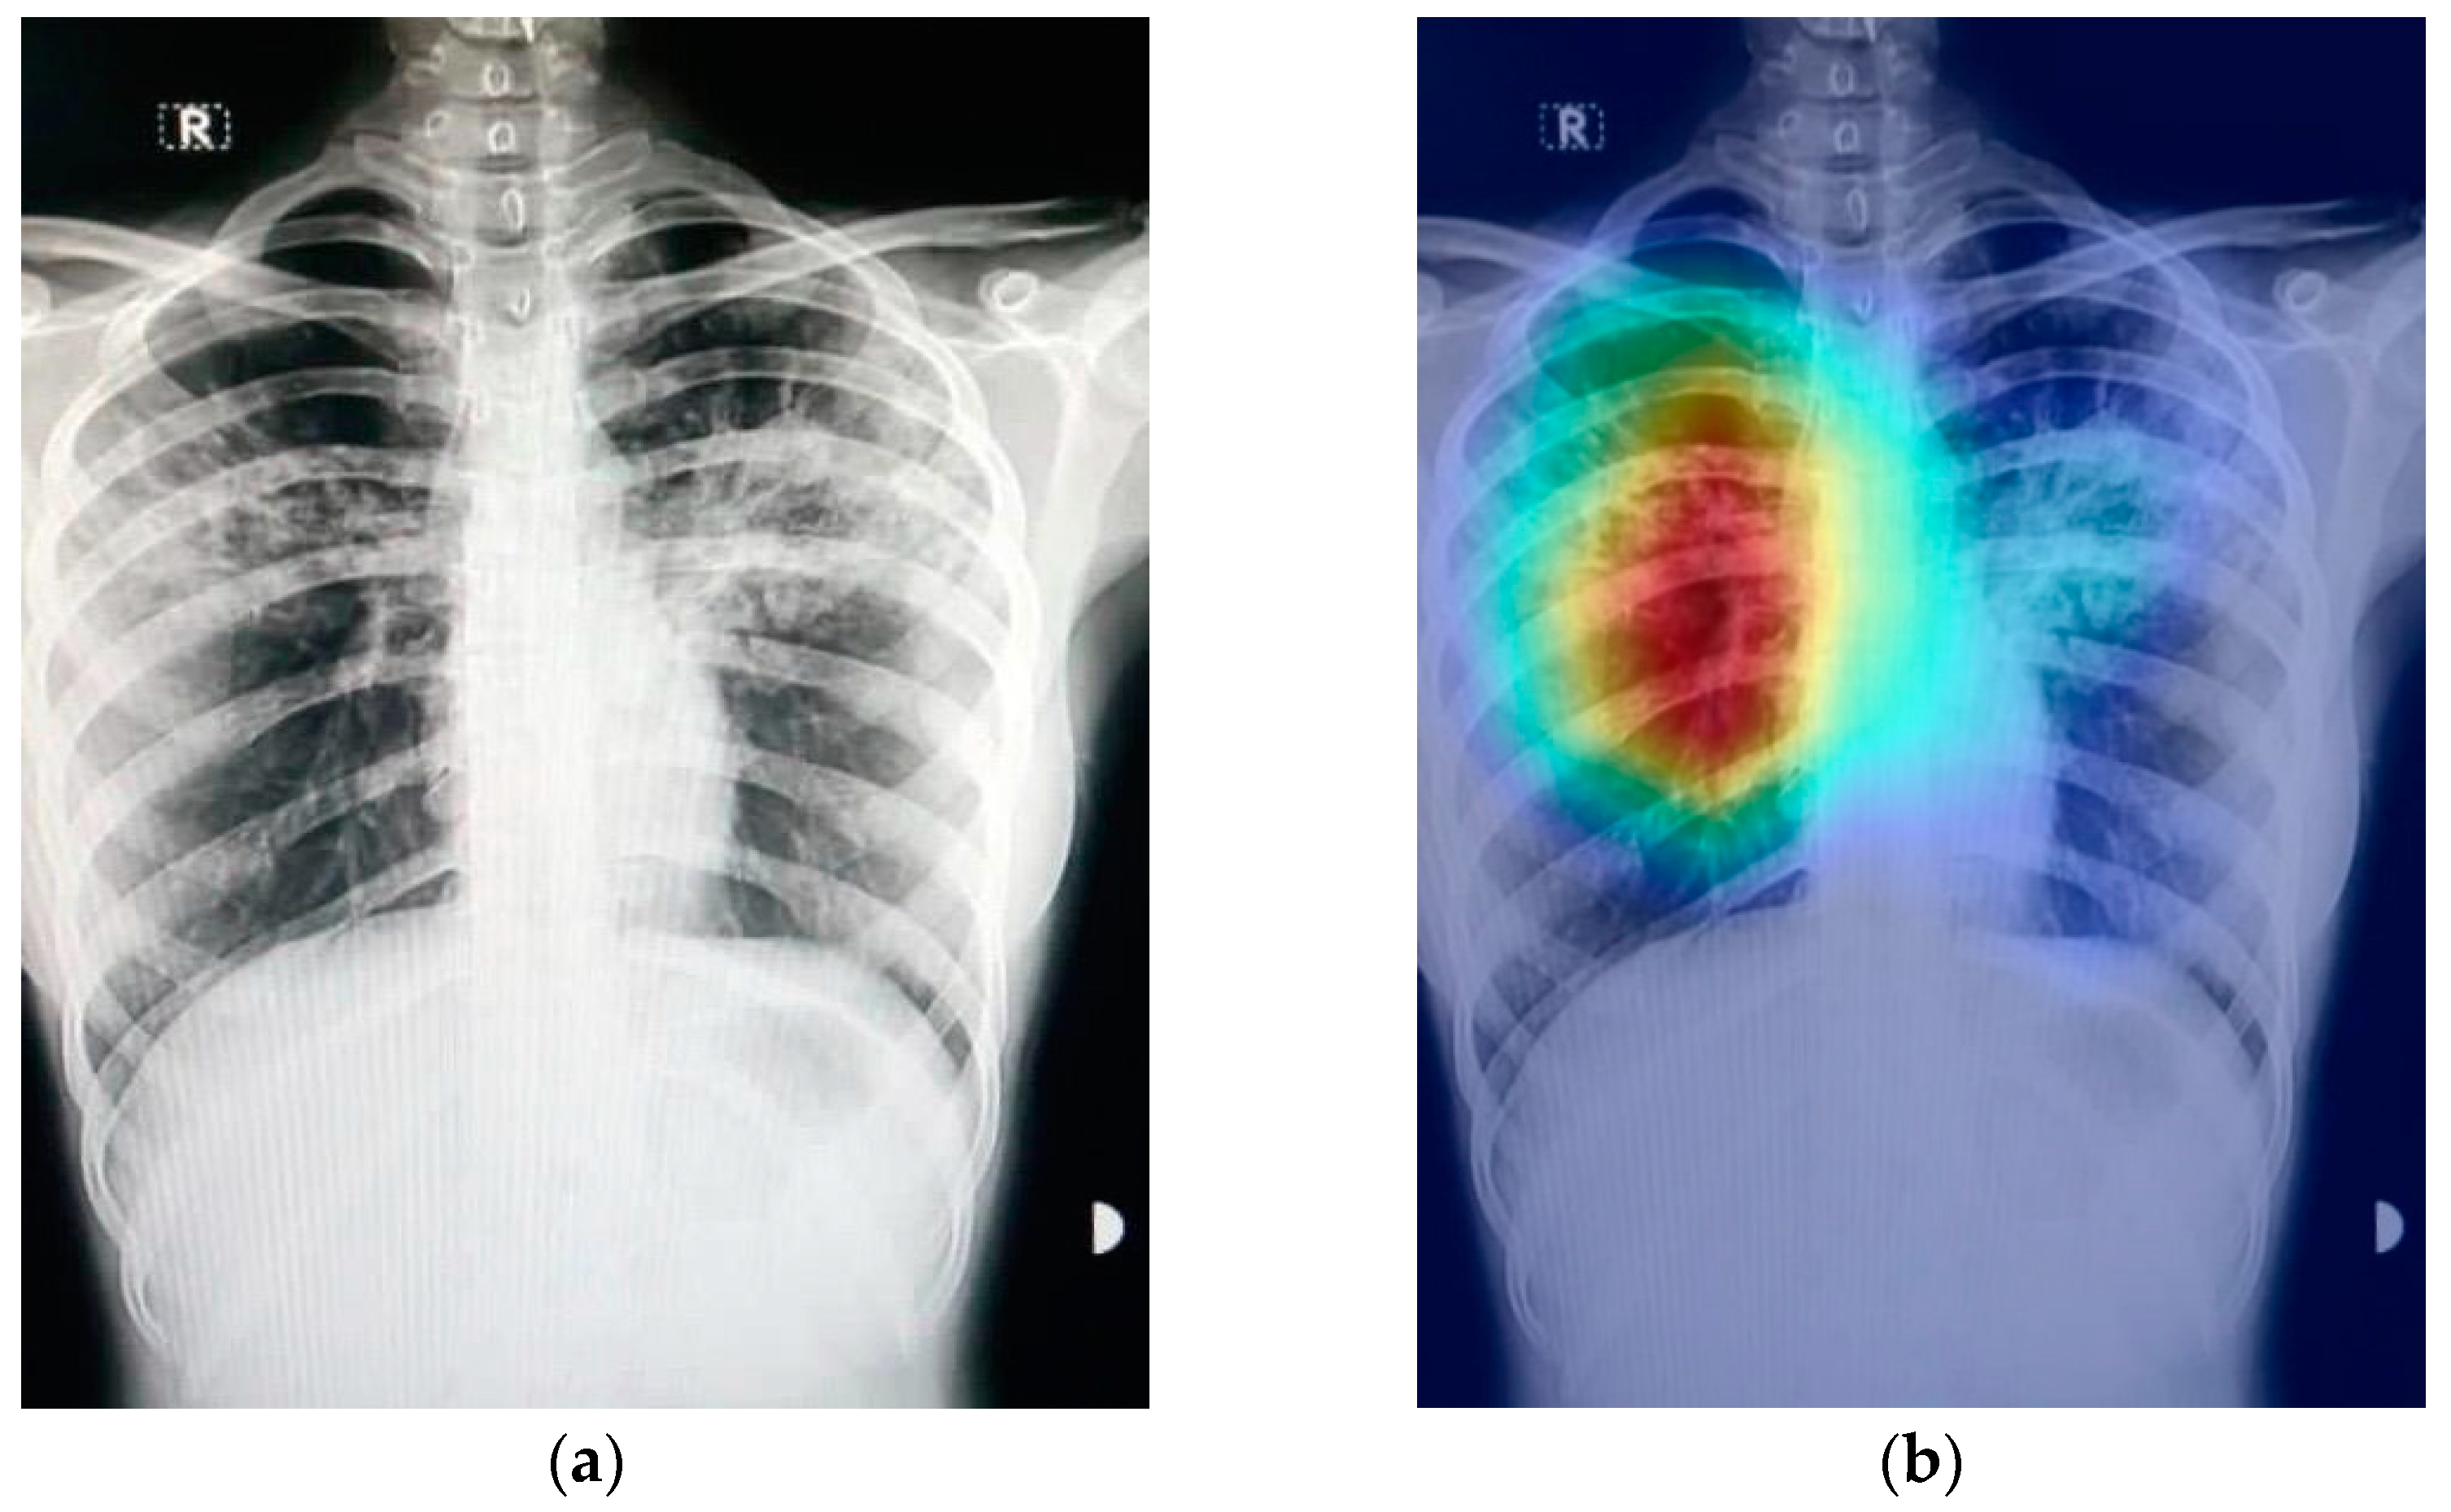

In CNNs, the gradient class activation map (Grad-CAM) is a technique that is used to create a class-specific heatmap. This generated class-specific heatmap is based on a specific input image using a trained CNN model [35]. The Grad-CAM technique is employed to figure out the COVID-19 detection transparency. This technique actually highlights the regions of the input image, which is where the model pays much attention during the classification process, implying the fact that the feature maps generated in the final convolution layer hold the spatial information that helps in capturing the visual pattern. This visual pattern contributes in distinguishing assigned classes. The Grad-CAM technique is applied by utilizing the layers and extracted features of the trained model. The architecture explaining the Grad-CAM technique is shown in Figure 8.

Figure 9 shows an example of a chest X-ray image generated using the Grad-CAM technique. The original chest X-ray image is shown in Figure 9a, whereas the overlay heatmap on the input image is shown in Figure 9b. The jet color scheme is used in this study. In this color scheme, blue tones represent lower values, which means that no features are extracted for a specific class, whereas the yellow and green tones represent medium values depicting quite less feature extraction, and the red and dark red tones represent larger values, i.e., the features in the region represent the specific class.

Figure 9.

Grad-CAM technique results on the COVID-19 X-ray image: (a) COVID-19 X-ray image; (b) Grad-CAM of the image.